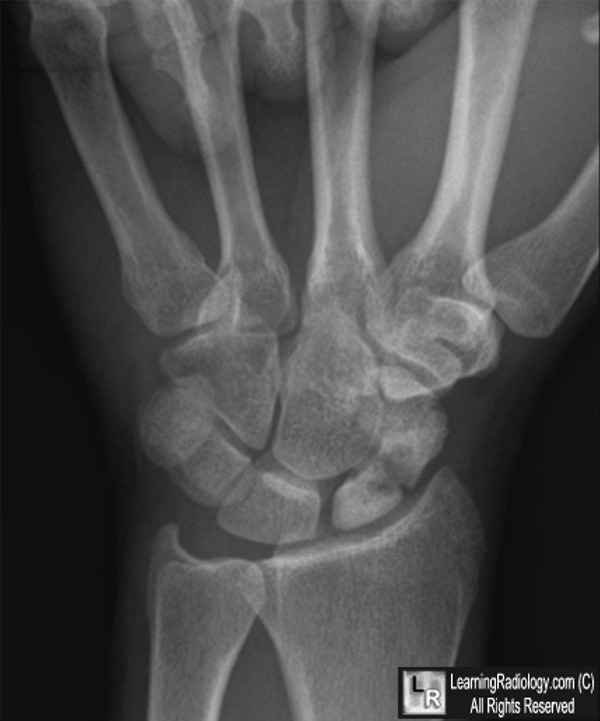

Avascular necrosis of the scaphoid secondary to fracture. Both photos: There is a transverse fracture of the waist of the scaphoid (yellow arrows) resulting in increased density of the proximal pole (white arrows) from avascular necrosis.

For these same photos without the arrows, click here and here